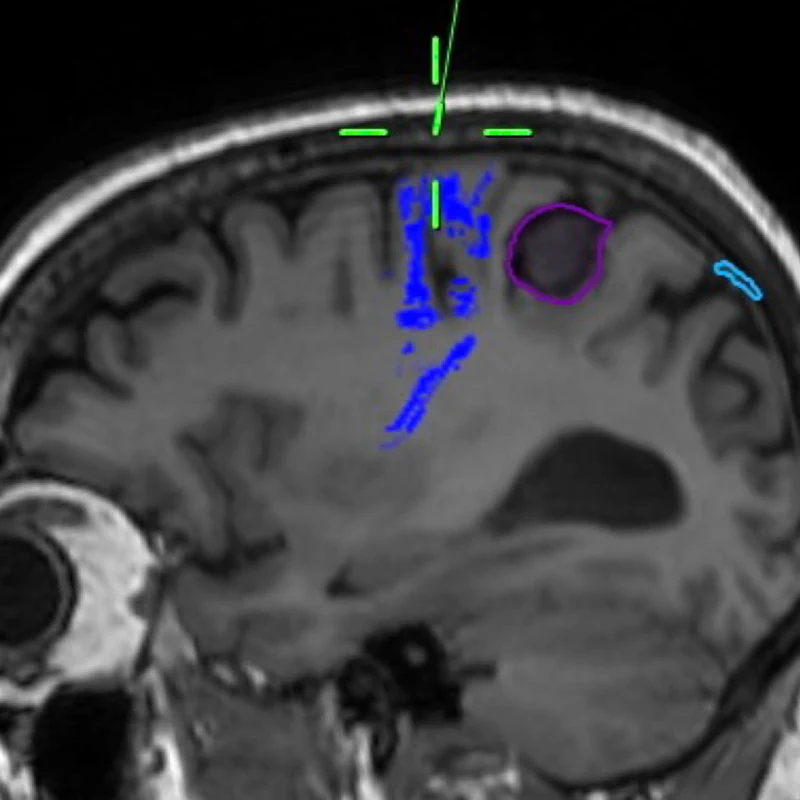

Figure 1. This composite figure illustrates intraoperative mapping of primary somatosensory cortex at high resolution using 2,048 surface microelectrodes.

Top Center. Sagittal T1-weighted brain MRI with tractography sequences based on diffusion-weighted imaging techniques. The corticospinal tracts descending from primary motor cortex are highlighted in blue, anterior to the tumor.